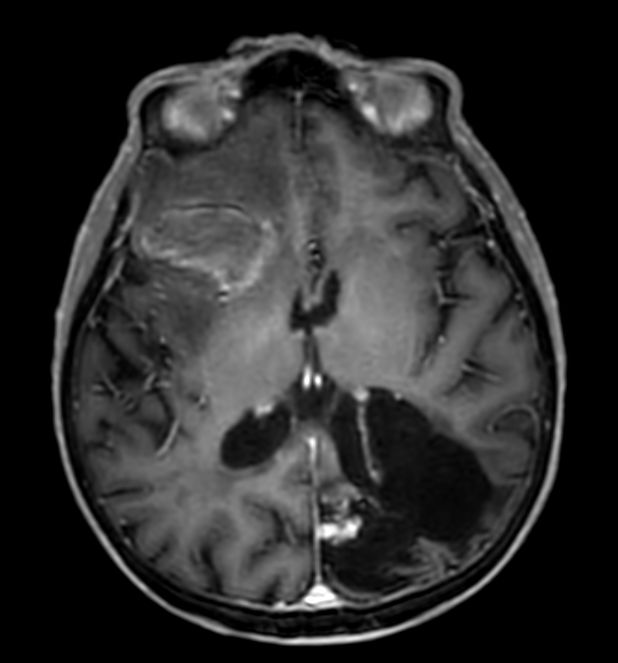

Sagittal 3D T1w FFE

3D T1w FFE (axial reformat)

3D T1w FFE (coronal reformat)